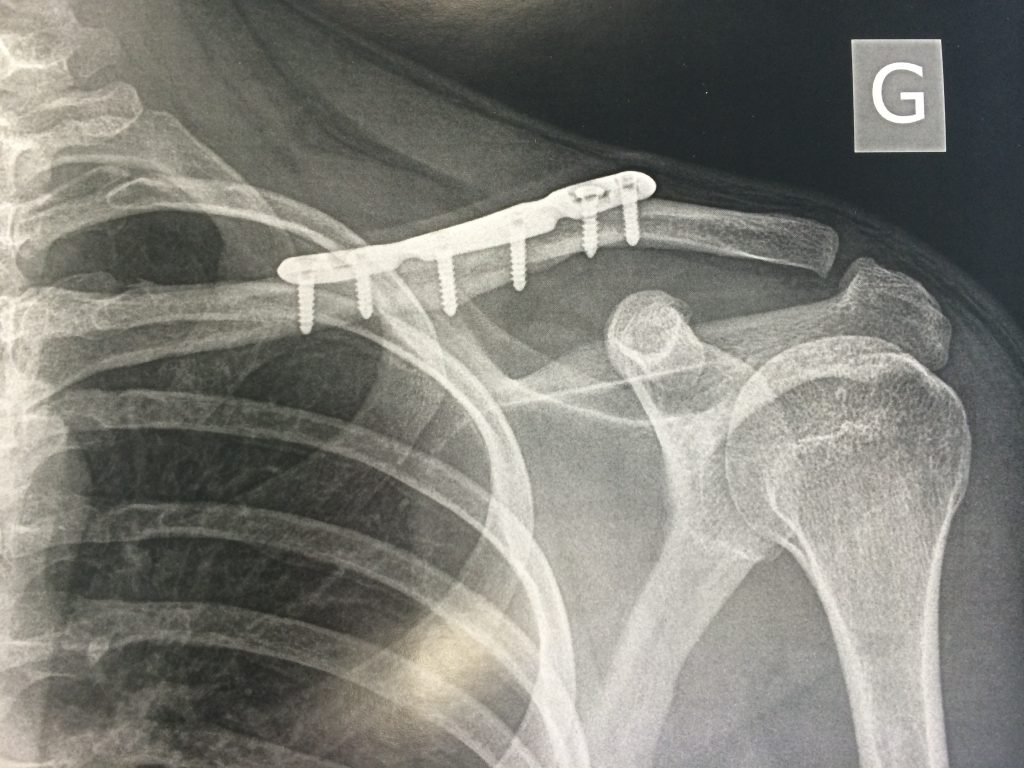

Fracture de la clavicule diagnostic, traitement. Dr Meryl Dahan

Les fractures de la clavicule Le site de l'épaule. Une ecchymose et un œdème peuvent également être présents. Quel est le temps de guérison d'une clavicule cassée ? En général, il faut bien 6 à 10 semaines pour guérir d'une clavicule cassée

Fracture de la clavicule Dr Sfez Chirurgien orthopédiste. La durée de guérison varie en fonction de plusieurs facteurs, tels que l'âge, le type de fracture et le traitement choisi Cependant, cette période peut être prolongée en cas de complications ou si.